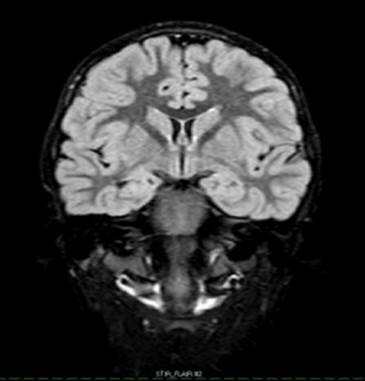

Preescolar masculino de 5 años de edad, quién es traído al servicio de urgencias, cuya madre refirió que había convulsionado (Verbatum de la madre). El paciente no tenía antecedentes patológicos conocidos. Inició enfermedad actual 2 horas previas a su ingreso, cuando durante sueño comienza a presentar súbitamente movimientos de inicio desconocidos a bilateral tónica- clónica con predominio en miembros superiores, postura en flexión, acompañado de retroversión ocular, menor de 1 minuto de duración. Posteriormente presentó postura flácida-hipotónica, sin respuesta al llamado y persistencia de la retroversión ocular por lo que madre realizó compresiones torácicas no cuantificadas y respiración boca a boca. Posterior a recuperación del estado de consciencia, presentó relajación de esfínter vesical y letargo, motivo por el cual deciden trasladarse al área de emergencia, donde fue evaluado decidiéndose su ingreso a observación. Dentro de sus antecedentes personales no había alteraciones en la adquisición de hitos del desarrollo, ni historia de crisis epilépticas previas. Acudía a terapia del lenguaje y cursaba 3er nivel de preescolar. Había sido inmunizado para varicela 1 semana previa al episodio. Padre y madre aparentemente sanos y no había historia familiar de epilepsia. Al examen físico el paciente se encontró en condiciones estables, con un peso 20 kg, temperatura de 36,2°C, tensión arterial en 110/84 mmHg, saturación de oxígeno en 99% aire ambiente, frecuencia respiratoria de 22 respiraciones/minuto y frecuencia cardíaca de 99 latidos/minuto. Se realizó glicemia capilar que reportó 119 mg/dL. Piel: fototipo III, turgor y elasticidad acordes a edad. Normocefálico, ojos con pupilas isocóricas con reflejos fotomotor y consensuado conservados. No se evidenciaron alteraciones en la esfera otorrinolaringológica. A la evaluación cardiopulmonar se evidenció un tórax simétrico, sin dificultad respiratoria, con ruidos presentes en ambos campos pulmonares y sin agregados. Los ruidos cardíacos se auscultaron rítmicos, sin soplos. Pulsos conservados. En el examen físico abdominal no había cambios al igual que a la evaluación de las extremidades. Neurológicamente se encontró sin signos de focalización, consciente, orientado en tiempo, espacio y persona, pares craneales conservados, reflejos osteotendinosos II/IV y fuerza muscular V/V, no había alteraciones de la marcha o de la coordinación, tampoco se evidenciaron signos meníngeos. Glasgow de 15/15 puntos. Se decidió ingresar bajo el diagnóstico presuntivo de crisis epiléptica generalizada, se indican laboratorios (hematología completa, proteína C reactiva, electrolitos séricos, antígeno y anticuerpos para SARS-CoV-2), los cuales se encontraban sin alteraciones, y se evidenció una IgG positiva para SARS CoV-2. Es evaluado por neuropediatría, decidiendo realizar EEG y RMNC. En el EEG (Figura 1) se reportó en vigilia, somnolencia y sueño evidenciándose anormal dado por actividad paroxística focal centrotemporal con amplio campo de propagación bilateral con moderada frecuencia de descarga y activado por el sueño. La RMNC (Figura 2) demostró adecuada diferenciación entre sustancia gris y sustancia blanca, sin cambios de intensidad de señal que sugieran proceso isquémico o hemorrágico, ni lesiones ocupantes de espacio, y el sistema ventricular estaba conservado. Se evidenció la asimetría de los hipocampos, con mayor tamaño del hipocampo izquierdo con respecto al derecho (Figura 2). En el contexto de una Epilepsia focal autolimitada de la infancia el paciente fué egresado con tratamiento con oxcarbazepina y citado para control de manera ambulatoria.

Figura 2: RMNC. Preescolar masculino de 5 años Secuencia Stair FLAIR 2. Corte coronal cerebral. Hipocampo izquierdo de mayor tamaño con respecto al derecho.

La Epilepsia focal autolimitada con puntas centrotemporales es uno de los síndromes epilépticos más conocidos2, que corresponde a un síndrome breve frecuentemente asociado a crisis de inicio focal con síntomas somatosensoriales, que tienen la tendencia a evolucionar a tónico-clónicas bilateral, se presentan con predominio durante el sueño. Puede afectar alrededor del 15-25% de los niños por debajo de los 15 años3 y el inicio de las crisis puede ocurrir entre los 3 a 13 años de edad siendo autolimitadas o farmacorrespondedoras. En algunos casos la remisión ocurre después de las primeras crisis epilépticas, o bien, después de los 15 años2. En el presente trabajo se reporta el caso de un preescolar masculino, quién presentó una primocrisis durante el sueño, caracterizada por movimientos de inicio desconocido a bilateral tónica-clónica y retroversión ocular, acompañado de relajación de esfínter vesical, correlacionándose con epilepsia focal autolimitada de la infancia. Se decidió realizar EEG, evidenciándose actividad paroxística focal centrotemporal con amplio campo de propagación que puede ser un hallazgo característico EA-PCT2, y en la RMNC se evidenció asimetría de hipocampos, dada por mayor tamaño del hipocampo izquierdo con respecto al derecho. La literatura mundial ha descrito asimetría y esclerosis hipocampal en niños con EA-PCT4. Si bien se desconoce la causa de esta asimetría se cree que puede ser multifactorial y es bien conocido que la esclerosis hipocampal es el hallazgo patológico más frecuente evidenciado en pacientes con epilepsia temporal médicamente intratable5. Se describe también que la asimetría hipocampal se puede evidenciar en pacientes con síndromes epilépticos que no incluyen estructuras mesiotemporales5.